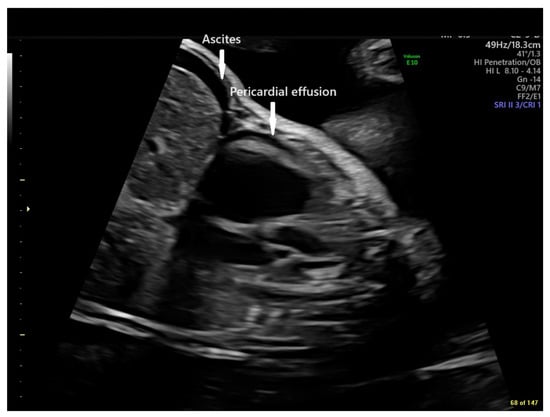

Fetal echocardiography was consistent with a diagnosis of Ebstein anomaly with severe tricuspid regurgitation and right atrial (RA) dilation, large tricuspid annulus dimension (Z score +3.5), right ventricular (RV) enlargement (diameter Z score +3.7), mild pulmonary annulus hypoplasia (Z score −2.7), pulmonary insufficiency with retrograde flow in a reverse-oriented ductus arteriosus, and normal branch pulmonary arteries (Figure 1). Tricuspid regurgitation jet velocity was low at 2.3 m/s [1,10,11], consistent with decreased right ventricular performance. At the time of consultation, the fetus was in a virtually incessant supraventricular tachycardia (long RP) with a rate of 203 bpm alternating with several beat runs of sinus vs. atrial rhythm with rates of 150–171 bpm. There was no evidence of fetal hydrops.

Figure 1. Panel (A): Paired fetal echocardiographic apical still frame images showing cardiomegaly, right atrial dilation, tricuspid annular dilation, and right ventricular enlargement at presentation at 28 6/7 weeks gestation. RA = Right Atrium, RV = Right Ventricle, LA = Left Atrium, LV = Left Ventricle. Doppler Color flow mapping superimposed on the panel at right demonstrates severe tricuspid insufficiency (arrow). Panel (B): Paired fetal echocardiographic sagittal still frame images of the dilated RV, the normal-sized RVOT, and the reverse-oriented ductus. RV = Right Ventricle, PV = Pulmonary Valve, MPA = Main Pulmonary Artery, LV = Left Ventricle, DA = Ductus Arteriosus. Doppler Color flow mapping in the panel at right demonstrates retrograde flow in the reverse-oriented ductus (blue), retrograde flow in the main pulmonary artery (orange), and marked pulmonary valve insufficiency (red). All images were produced on a GE Voluson E10 Ultrasound System.